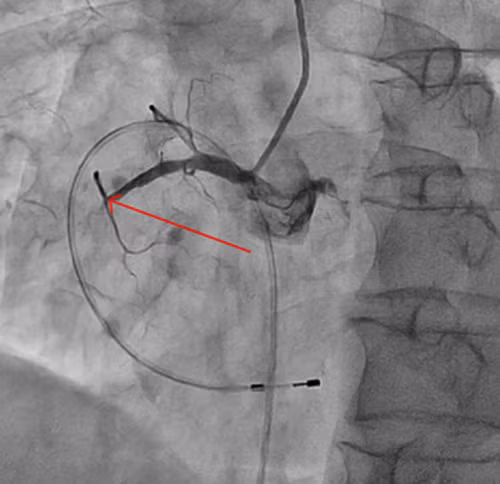

| Đoạn động mạch vành phải bị tắc hoàn toàn (vị trí mũi tên chỉ); |